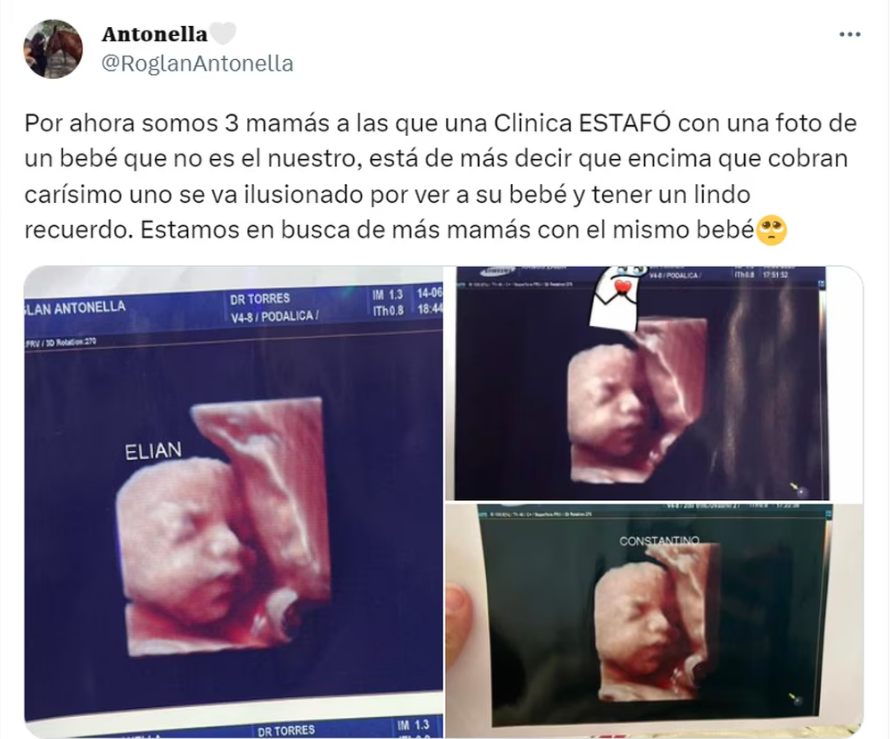

“Por ahora somos 3 mamás a las que una clínica estafó con una foto de un bebé que no es el nuestro”, reclamó Antonella Roglan en Twitter. Además, adjuntó las tres fotografías.

“Está de más decir que encima que cobran carísimo, uno se va ilusionado por ver a su bebé y tener un lindo recuerdo. Estamos en busca de más mamás con el mismo bebé”, agregó. “Ya nos había dicho algo, pero nos resistíamos a creer”, explicaron las víctimas.